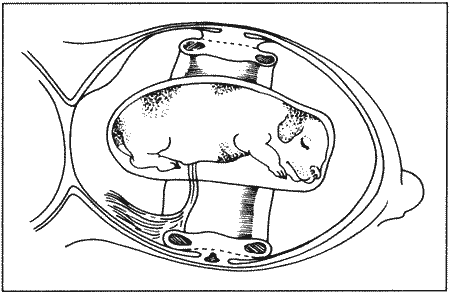

На стадии метэструса происходит развитие эмбрионов; интересно отметить согласованность протекания некоторых основных этапов, предшествующих имплантации, и продемонстрировать их связь с изменениями концентрации прогестерона и эстрадиола (фиг. 1.1). Наиболее целесообразно принять за точку отсчета овуляторный пик ЛГ. Как уже упоминалось, овуляция происходит на 2 день, после чего яйцеклетки проходят период созревания. К 4–7 дню они готовы к оплодотворению. Оплодотворенные яйцеклетки некоторое время удерживаются в маточных трубах, они проходят маточно-трубное соединение и приблизительно на 10 день перемещаются в рога матки. Увеличение соотношения прогестерон/эстрадиол (фиг. 1.1), судя по всему, имеет жизненно важное значение для этого этапа. Бластоцисты локализуются в роге матки вплоть до 13 дня, после чего свободно мигрируют из одного рога в другой до 16 дня, когда набухание эндометрия свидетельствует о том, что имплантация эмбрионов произошла.

Овуляция и оплодотворение

После вязки с фертильным самцом или успешного искусственного осеменения эмбрионы в течение 4–5 дней после оплодотворения развиваются в маточных трубах, затем мигрируют в рог матки, где приблизительно на 12–16 день после повторной вязки (первая необходима для индукции овуляции) происходит имплантация. Перед имплантацией бластоцисты свободно перемещаются в полости матки, мигрируя из одного рога в другой, вероятно, такая миграция обеспечивает равномерное распределение эмбрионов в полости матки. Считая от момента имплантации, беременность продолжается еще 50 дней, таким образом, общая продолжительность беременности составляет около 64 дней (от даты первой вязки). Секреция прогестерона во время беременности — как и в случае ложной беременности — препятствует наступлению эструса.